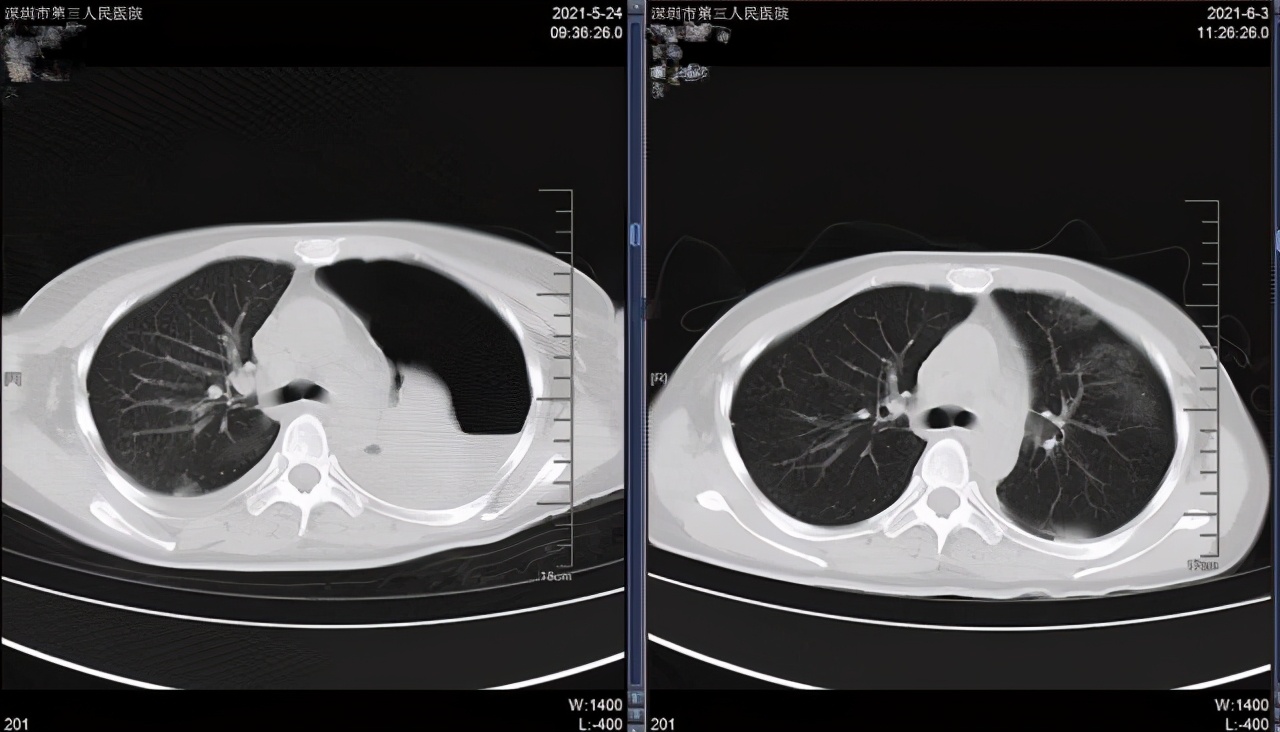

▲袁女士肺部治疗前后 CT 对比图

袁女士入院时身体状况差,自身抵抗力低下,左侧支气管内膜结核使她出现了严重的左肺不张(即各种原因引起的肺组织塌陷)。左肺被压缩到只剩 10% 至 15% 在正常工作,加上脊柱结核带来的疼痛感,她每一次的呼吸都相当困难。

医生认为,首先要缓解袁女士的呼吸问题,解除左侧支气管阻塞使左肺复张,增加袁女士的呼吸容积,再进行下一步的治疗。经过纤支镜室两次支气管镜下治疗,袁女士左肺复张到了 60%,呼吸困难症状明显好转。

此后,袁女士继续在纤支镜室进行了支气管镜镜下治疗,改善支气管阻塞的情况。经过 3 次治疗,左肺已经复张至 90% 左右。